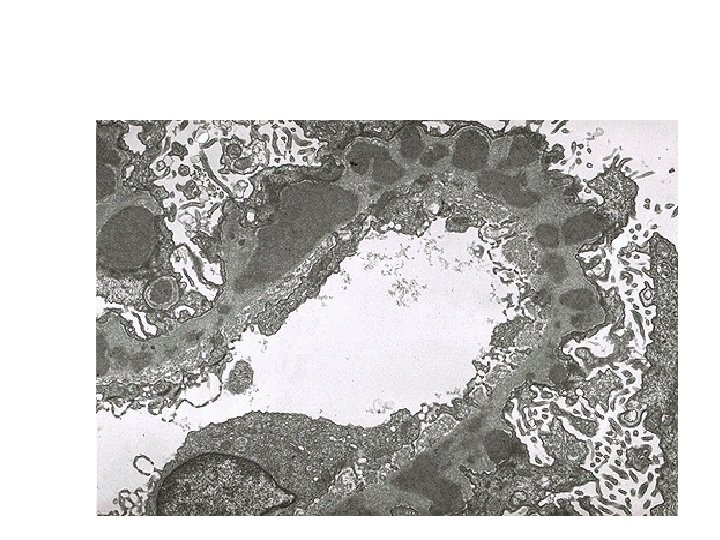

Electron microscopy - Ruptures in the GBM in the three groups - Shows discloses deposits in those cases due to immune complex deposition (type II). Note: - In time, most crescents undergo organization and fibrosis

Electron microscopy - The thickening is seen to be caused by irregular electron dense also deposits containing immune complexes between the basement membrane and the overlying epithelial cells, with effacement of podocyte foot processes

- Basement membrane material is laid down between these deposits, appearing as irregular spikes protruding from the GBM - These spikes are best seen by silver stains, which color the basement membrane, but not the deposits, black

- In time, these spikes thicken to produce domelike protrusions and eventually close over the immune deposits, burying them within a markedly thickened, irregular membrane.